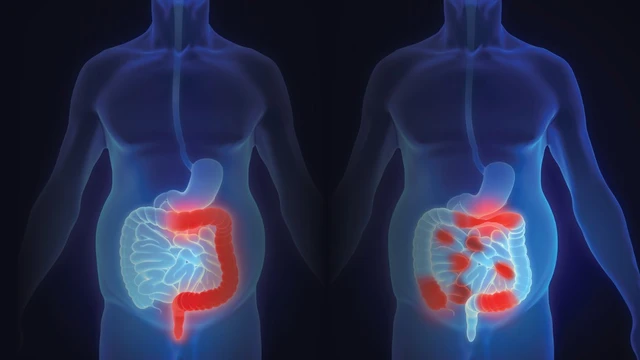

/https://cms-prod.s3-sgn09.fptcloud.com/phan_biet_viem_ruot_thua_va_benh_tui_mat_553dce472c.jpg)

Phân biệt viêm ruột thừa và bệnh túi mật dựa trên vị trí đau, triệu chứng kèm theo và dấu hiệu cảnh báo giúp chẩn đoán chính xác, điều trị kịp thời, tránh biến chứng nguy hiểm. Cùng tìm hiểu cụ thể trong nội dung bài viết sau đây.